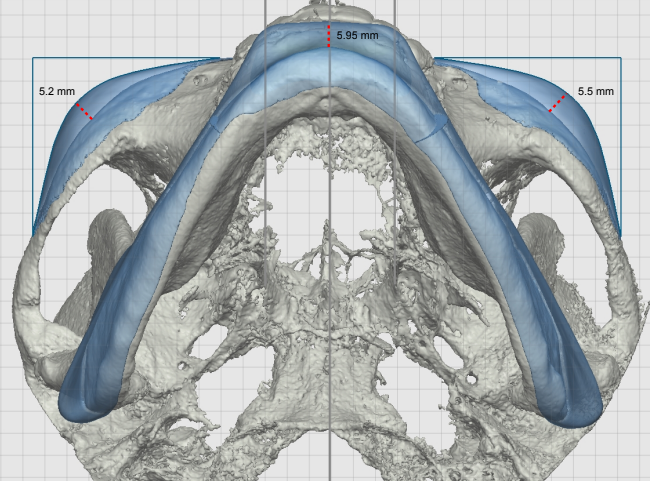

Recently got this implant design from Dr. Y for custom mandible (jaw & chin) and malar / cheekbones with infraorbital rims.

this design is good, do not listen to that moron who drew on the back edge of the implant. there is no need to augment past the suture and your cheek is an oblique, the prominence has a good amount of projection, though you could prob push him to go a bit further. dr y doesn't love ridiculous patient involvement but you might be able to get him to go bigger by 2mm at the most prominent point to go from 5-7.

@zeek The design says they are ~5.5 at the most prominent point I believe. Also, I consider my cheekbone area much better than average - Dr. Y himself said 'You know your malar area isn't as bad as you think'. That in conjunction with the fact I provided pictures of Toni Mahfud and Mario Rodriguez as reference makes me confident that his design will be plenty. He also gave me the impression that he was doing a bit 'more' with my particular design and that the result will be spot on with the Mahfud & Rodriguez look. Love the design, it's like a fusion of both Mahfud's and Rodriguez's midface and lower-third.